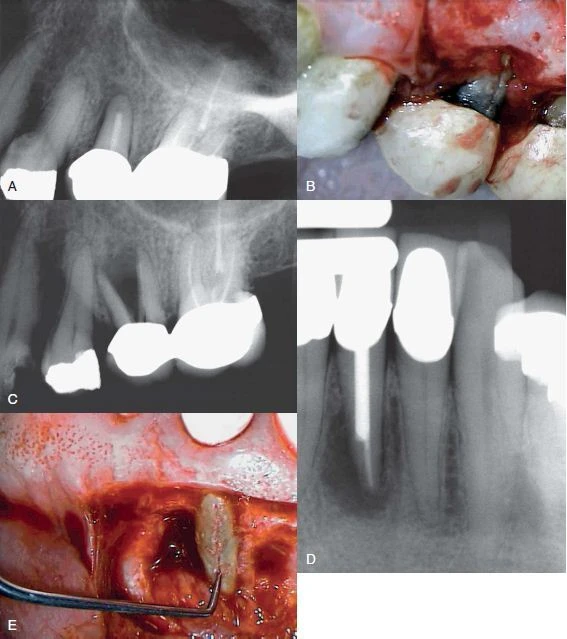

Thông thường cách duy nhất để xác định xem liệu có nứt dọc chân răng không là phẫu thuật bộc lộ trực tiếp. Để quan sát tốt vùng nghi ngờ có nứt răng, bác sĩ cần lật vạt đủ độ dày đến màng xương, bắt đầu từ rãnh nướu đi về phía chóp. Thông thường, chỉ cần một vạt nhỏ là đủ, một khi đã lật vạt, nếu có nứt dọc chân răng thì có thể thấy được vết nứt sau khi loại bỏ mô hạt nằm bên trên. Nhiều khi có một vùng nứt xương liên quan đến vết nứt dọc chân răng. Sử dụng kính hiển vi điện tử nha khoa để chiếu sáng và giúp quan sát tổn thương tốt hơn.

Hình 8. Khi nghi ngờ nứt dọc chân răng, đôi lúc phải lật vạt để quan sát tốt hơn.

Hình ảnh mất xương như “vòng sáng”

Thông thường khi một răng chết tuỷ thì hình ảnh X quang của nó sẽ thay đổi, mất xương xảy ra ở vùng chóp. Tuy nhiên, khi một răng bị nứt dọc hoặc chia chân răng, vùng mất xương có khuynh hướng cho hình ảnh “vòng sáng”, thấu quang xung quanh chân răng. Vùng thấu quang cũng có thể đi dọc toàn bộ một bên chân răng và thường được gọi là tổn thương “dạng chữ J”.

Hình 13. Hình ảnh tiêu xương “dạng chữ J”

Vùng mất xương khu trú

Bác sĩ cần chú ý đến những thay đổi bất thường trên X quang như mất xương rộng nhưng chỉ khu trú ở một răng và không có bệnh lý nha chu tiến triển. Điều này có thể gợi ý nứt dọc chân răng hoặc chia chân răng. Khi nghi ngờ có nứt dọc chân răng, bác sĩ cần chú ý tìm những dấu hiệu sau:

- Vùng mất xương ở phía gần và xa chân răng. Khi nứt dọc chân răng hoặc chia chân răng mở rộng từ phía gần đến phía xa của răng thì thường toàn bộ dây chằng nha chu quanh răng sẽ giãn rộng không điển hình

Hình 14. Tiêu xương rộng khu trú quanh một răng, những răng cạnh đó bình thường, gợi ý một trường hợp nứt dọc chân răng